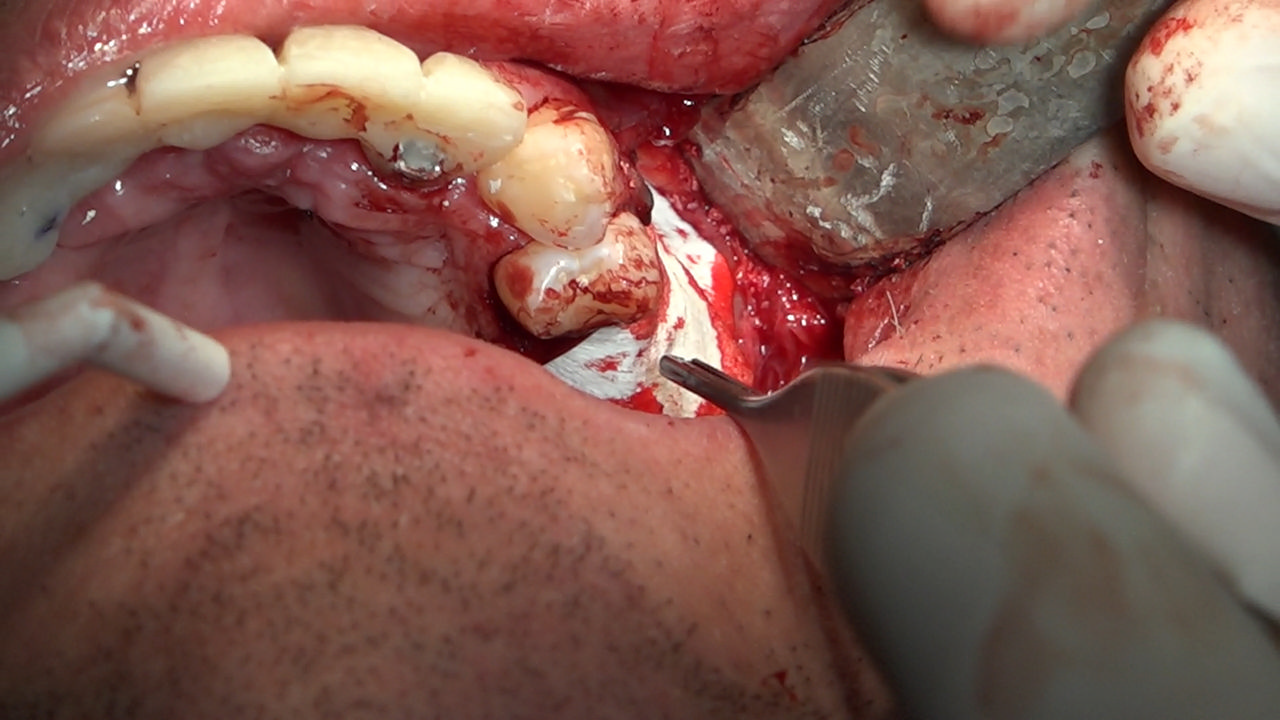

PRACTICULUM IMPLANTOLOGII - SEZON X - SESJA 7

7 Sesja X Sezonu Practiculum Implantologii, w której brali udział kursanci z Grupy A i B, obejmowała implantacje wykonane systemem Axiom, procedury regeneracyjne tkanki kostnej i zabieg sinus lift oraz procedury implantoptotetyczne. Ten zakres szkolenia poprowadziła dr Małgorzata Piotrowska. Protetyka na implantach, to finalny etap leczenia implantologicznego decydujący o uzyskaniu harmonijnego łuku zębowego, okluzji oraz szczelności połączeń, a więc zadowoleniu Pacjenta i powodzeniu całego procesu leczenia.